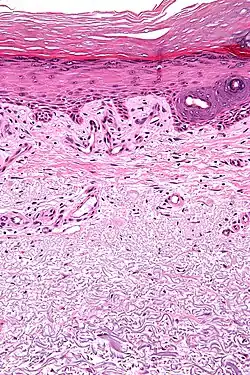

Micrograph showing solar elastosis - grey, jumbled spaghetti-like material on bottom of image. H&E stain.

Solar elastosis separates from the epidermis by a narrow band of normal-appearing collagen (grenz zone) with collagen fibers arranged horizontally.[1]

In the earlier stages of actinic elastosis, elastic fiber proliferation can be seen in the dermis. As the condition becomes more established, the collagen fibers of the papillary dermis and reticular dermis become increasingly replaced by thickened and curled fibers that form tangled masses and appear basophilic under routine haematoxylin and eosin staining. These fibers stain black with the Verhoeff stain.[2]